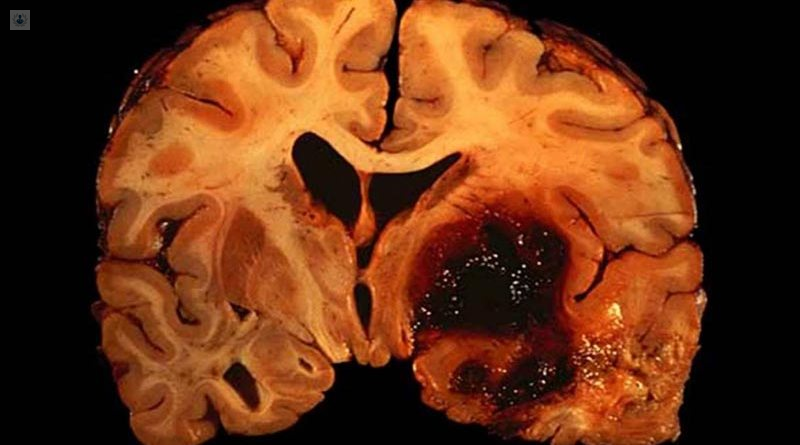

Un derrame cerebral es un evento en el que un vaso sanguíneo del cerebro se rompe y sangra dentro, aumentando la presión en el cráneo, causando inflamación del tejido cerebral y dañando las células. Se necesita atención médica de emergencia.

Y s que si una hemorragia cerebral no se trata a tiempo, las lesiones cerebrales pueden llevar a los pacientes a la muerte o a dejarlos con lesiones graves que tienen como consecuencia una discapacidad.